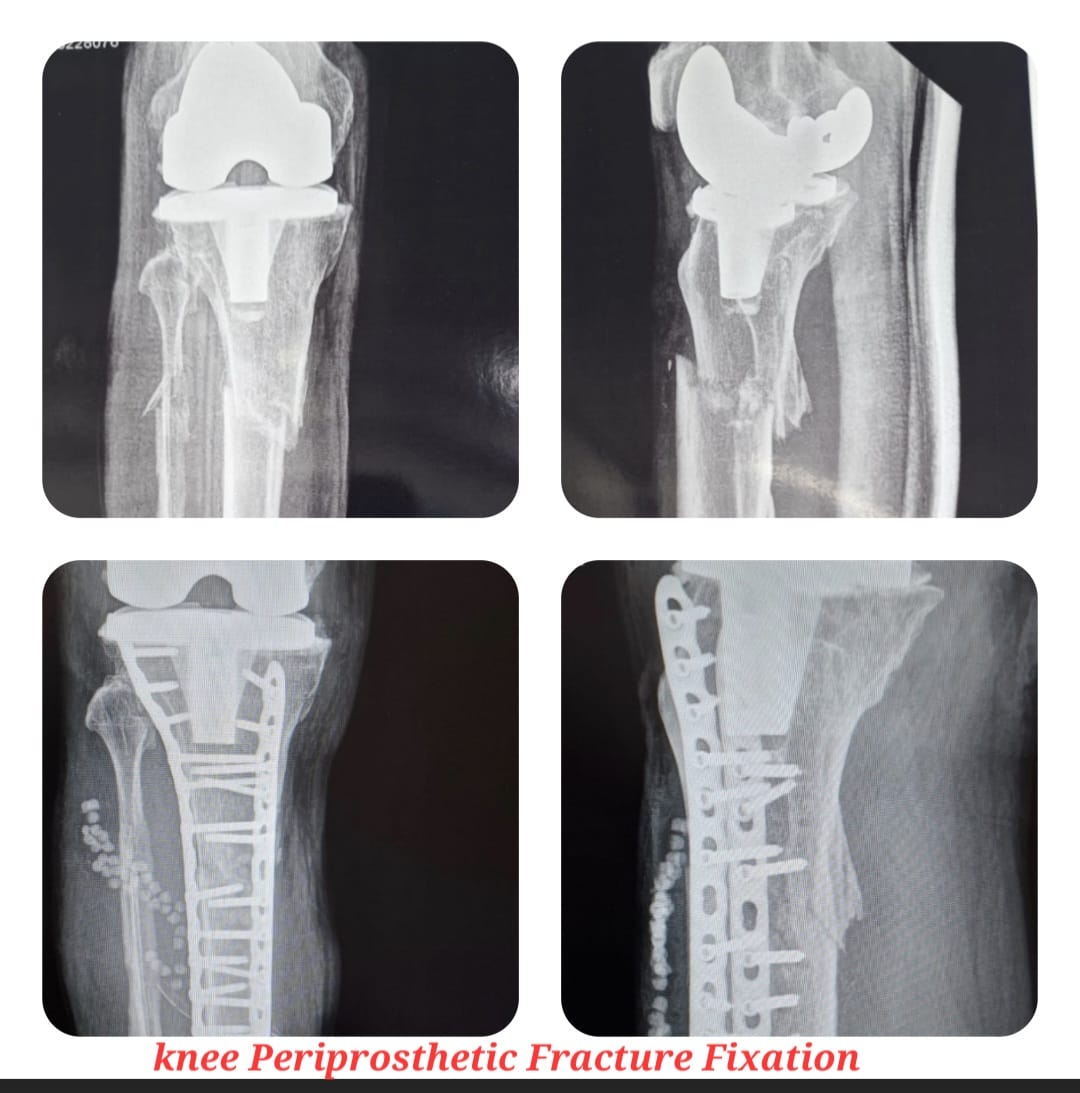

Diagnosis begins with detailed clinical evaluation supported by advanced imaging such as X-rays, CT scans, and MRI. Treatment options are customized based on the type and severity of injury and may include casting, splinting, closed reduction, or surgical intervention to restore proper alignment and stability.